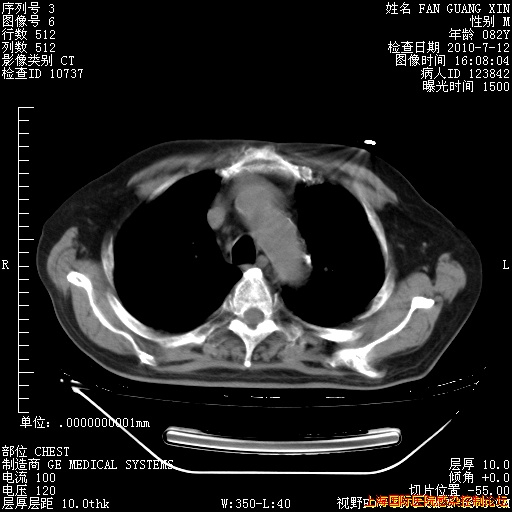

6月12日纵膈窗